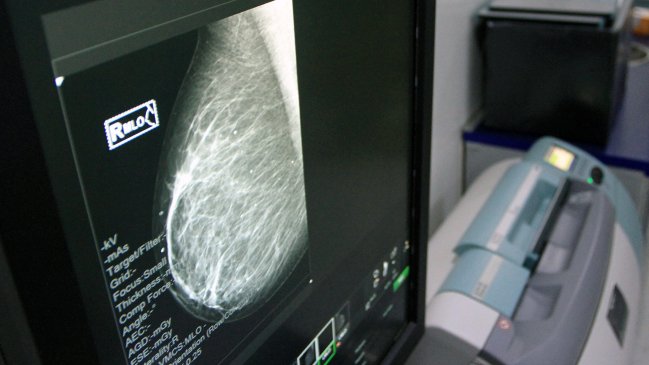

Suprema ordenó al Minsal entregar droga para paciente con cáncer de mama

El Minsal debe financiar y proporcionar a Prado Martí el medicamento Herceptin.

La Corte Suprema ratificó el fallo de la Corte de Apelaciones de Santiago que ordenó al Ministerio de Salud brindar tratamiento con el medicamento Herceptin (Trastuzumab), a una mujer con cáncer de mama.